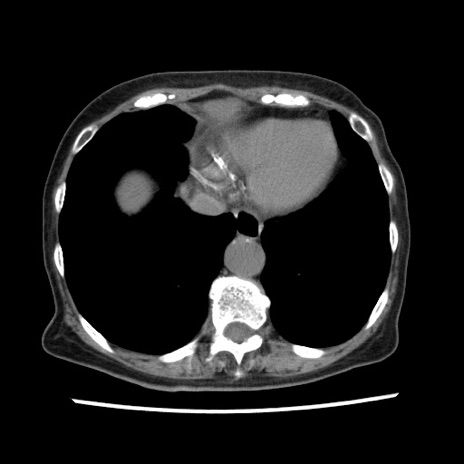

冠状断像